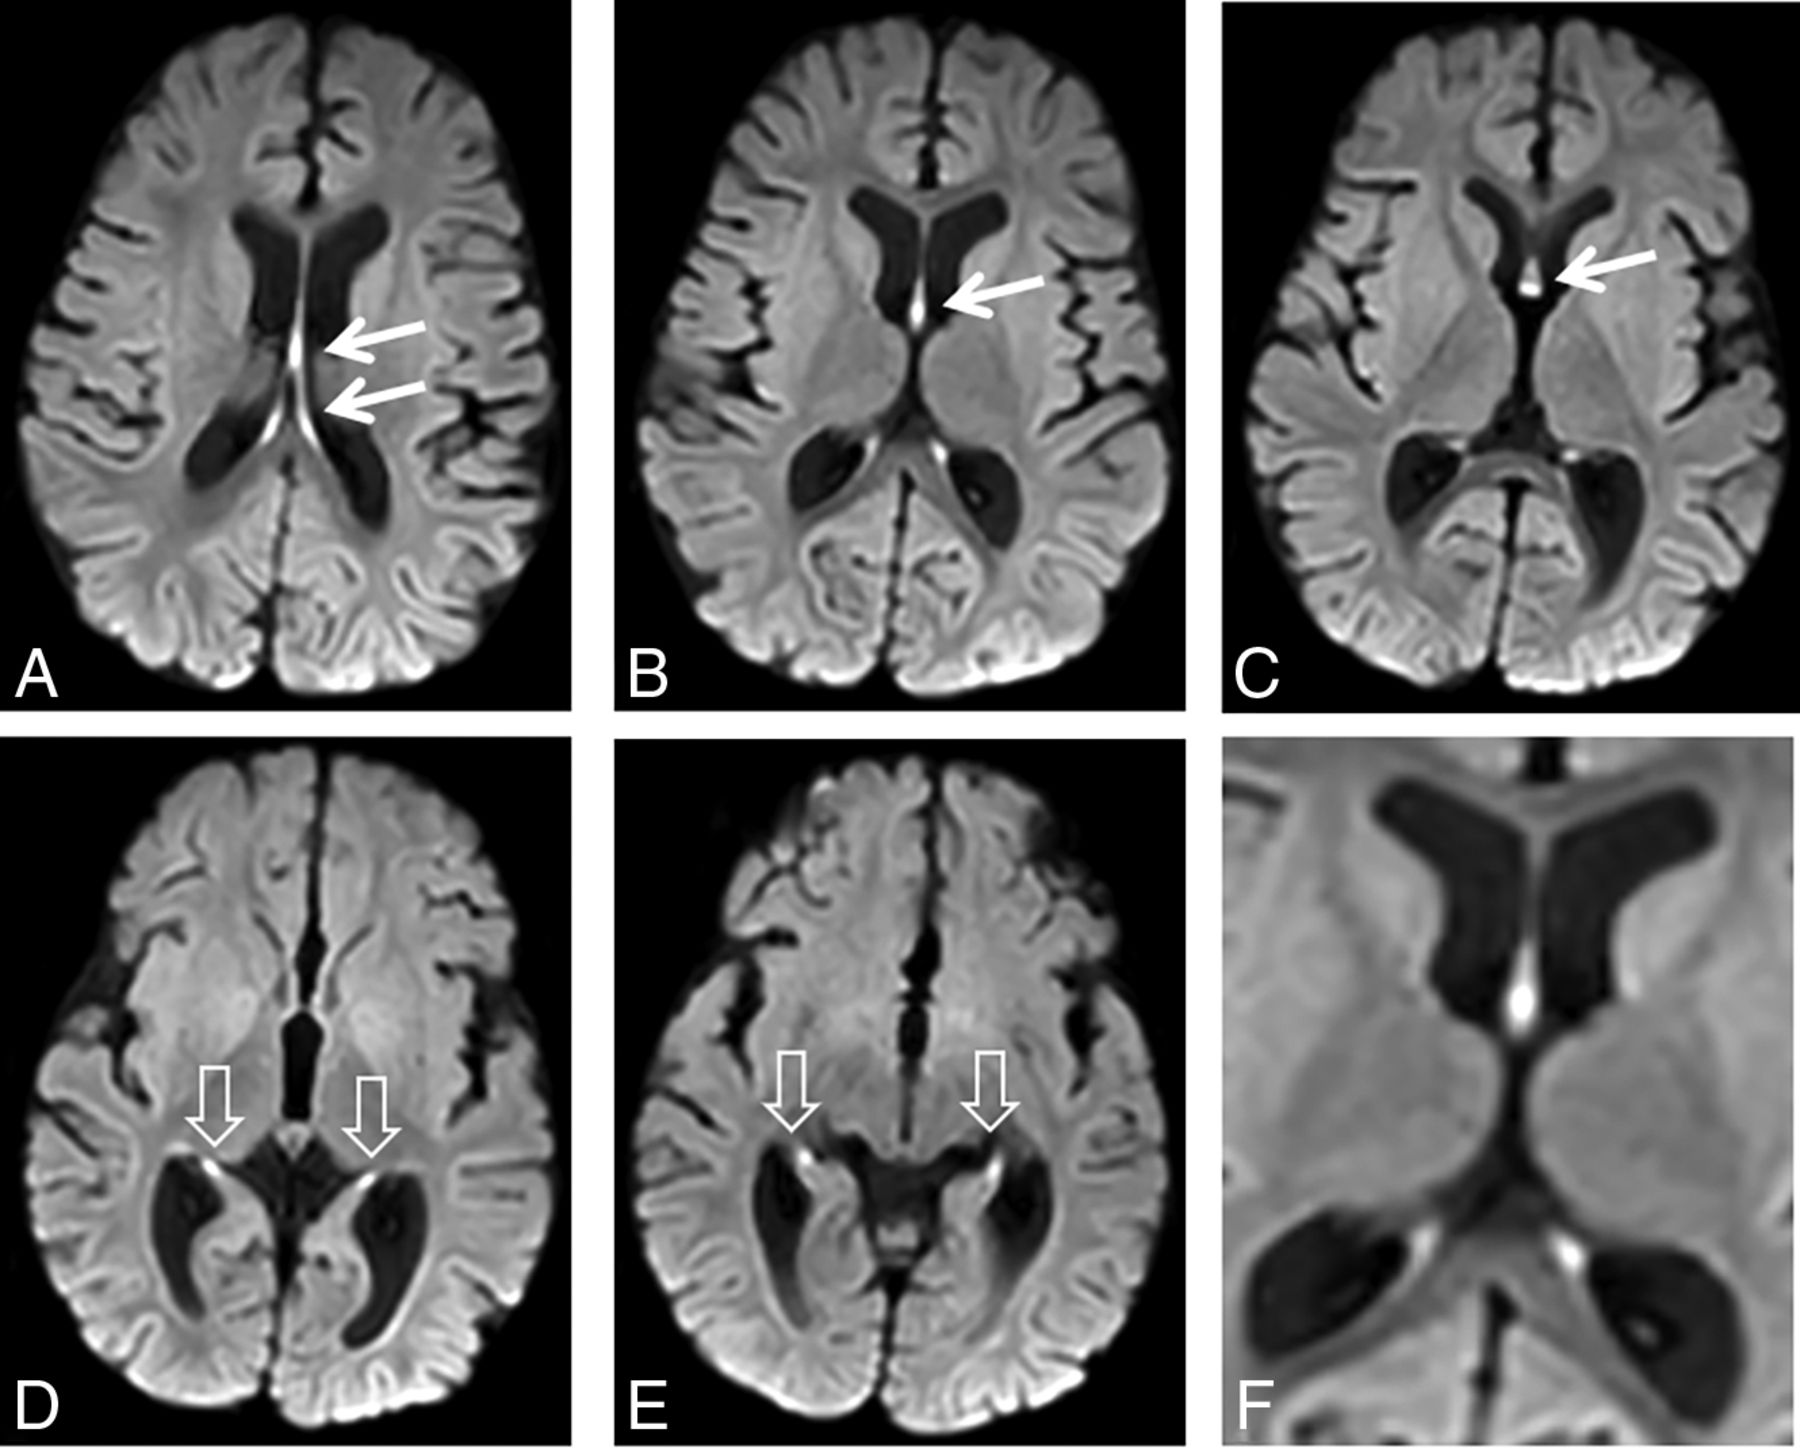

DWI signal hyperintensity in the fornix-fimbria. MR imaging study of a 7.5-month-old girl with hypsarrhythmia. Consecutive diffusion-weighted images from top (A) to bottom (E) show signal hyperintensity of the fornices (arrows) and fimbriae (arrowheads). F, A magnified view shows DWI hyperintensity involving the fornix-fimbria complex. Also notable is mild volume loss.